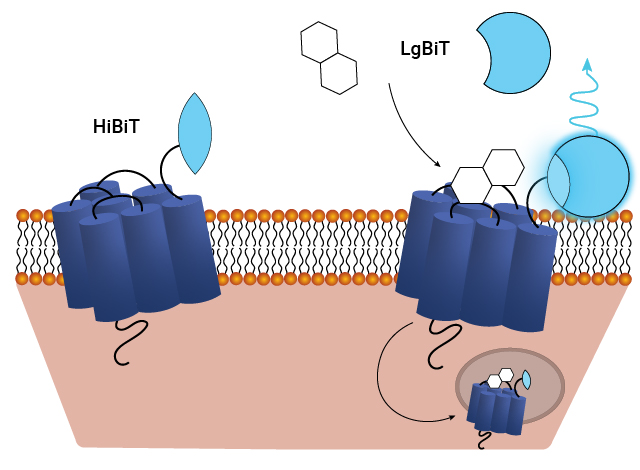

GPCR internalization is a key regulatory process that controls receptor availability and signaling dynamics. After ligand binding and activation, receptors are internalized into endosomes, where they can either be degraded or recycled back to the cell surface. Recycling restores GPCR availability, ensuring sustained cellular responsiveness and signaling balance, making it a critical aspect of drug discovery and therapeutic design.

Measure GPCR Internalization in Real Time

The Nano-Glo® HiBiT Extracellular Detection System is an easy way to quantify proteins expressed on the cell surface in real time. This antibody-free HiBiT tag-based approach allows you to measure receptor internalization and subsequent recycling and eliminate the variability associated with antibody-based methods. See details in this white paper: Quantifying Percent Surface Expression Using Bioluminescent Detection of the HiBiT Protein Tag

Schematic of assays utilizing the HiBiT/LgBiT reporter for monitoring ligand-induced GPCR internalization. See details in this publication: The luminescent HiBiT peptide enables selective quantitation of G protein-coupled receptor ligand engagement and internalization in living cells.